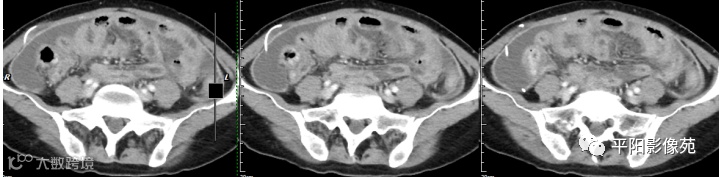

腹部增强 动脉期